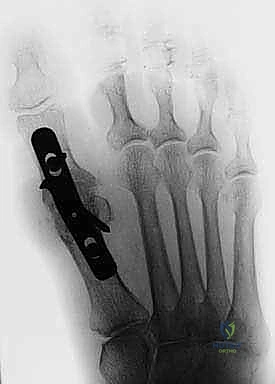

Given the lack of significant rates of loosening seen with this implant, recent FDA approval has been obtained for a novel total toe arthroplasty design (Arthrosurface ToeMotion Total Toe Arthroplasty) using the same tapered screw fixation method within proximal phalanx (FIG 9). A proximal phalangeal component with polyethylene insert was created as a complement to the metatarsal HemiCAP DF implant in an effort to address progressive arthritic changes of the proximal phalangeal articular surface. When significant involvement of both sides of the joint are seen at the time of the index procedure, use of the ToeMotion total toe arthroplasty design would be more appropriate than a hemiarthroplasty alone with the desired goal of providing a more predictable procedure for pain relief.

FIG 9 • A. Arthrosurface ToeMotion total toe arthroplasty implant. Inlay arthroplasty using taper screw-based fixation and modular polyethylene insert. (continued)

FIG 9 • (continued) B-E. Radiographs of ToeMotion total toe arthroplasty.